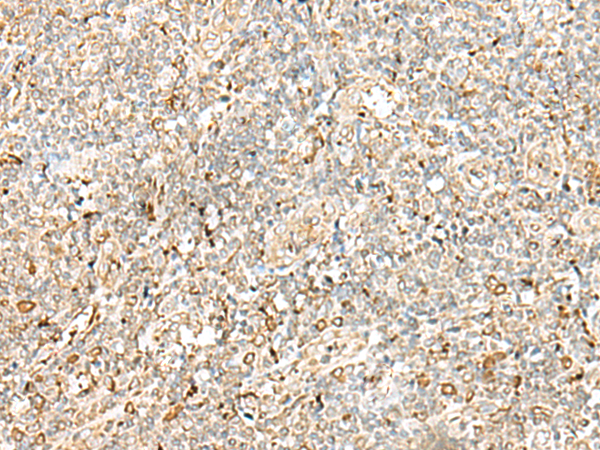

分类: 科研抗体货号: P09954别名: a1; Stv1; VPP1; Vph1; ATP6N1; ATP6N1A应用: IHC反应种属: Human, Rat